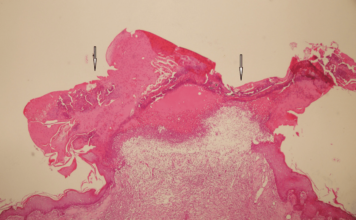

Представлен новый способ лечения акне

Сегодня специалисты из Лондонского Королевского Колледжа представили результаты своего длительного по времени и комплек...